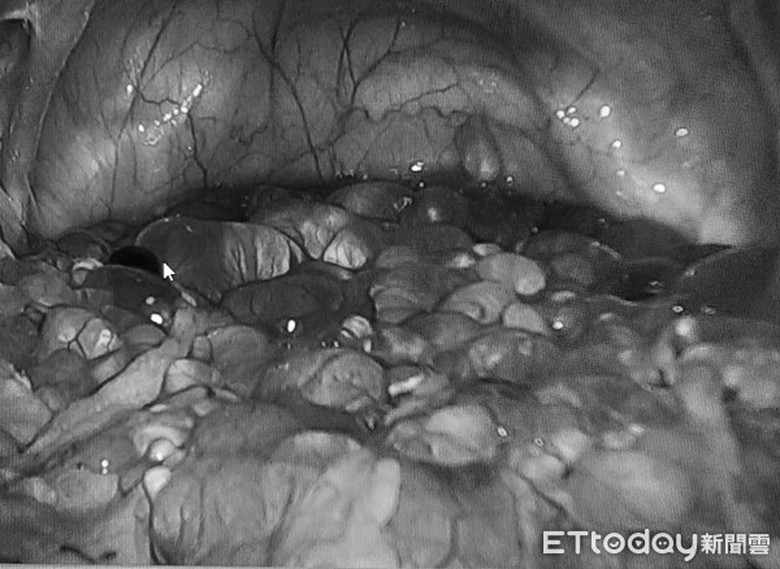

Bác sĩ Lý chia sẻ, đây là lần đầu tiên ông quan sát và thấy có vấn đề về kết dính trong dạ dày nữ bệnh nhân thông qua nội soi. Nếu ống dẫn trứng có thể được tách và mở ra, vấn đề vô sinh sẽ được giải quyết. Thế nhưng, khi quan sát sâu bên trong, bác sĩ hoảng sợ khi nhận thấy có rất nhiều “khối tròn trông giống như ngọc trai” trong khoang chậu. Đây là dấu hiệu đặc trưng của ung thư buồng trứng.

Hàng trăm u nang trong khoang chậu của phụ nữ.

Sau khi hội chẩn, bác sĩ Lý nhận định đây là một khối u lành tính, những u nang trong cơ thể bao trùm bất thường. Có quá nhiều u nang dính chùm với nhau như những viên bột trân châu, bám đầy quanh sàn chậu.

Bác sĩ Lý cho biết, trước đây ông chỉ thấy một số u nang nhỏ dính ở vùng phụ cận của ống dẫn trứng. Trường hợp của người phụ nữ này là nghiêm trọng nhất, có đến hàng trăm u nang lớn nhỏ chứa chất lỏng. Sau ca phẫu thuật, kết hợp với uống kháng sinh, bệnh tình của nữ bệnh nhân tiến triển tốt, không có dấu hiệu tái phát.